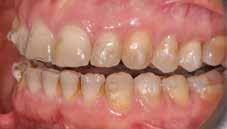

A fogazat elhasználódása alatt azoknak a degeneratív folyamatoknak az összesített hatását értjük, melyeken az élet során a szervezet keresztülmegy. Ezek lehetnek a fogérintkezések közben fellépő mechanikai erők (abrázió, attríció), endogén vagy exogén eredetű savas közegek által kiváltott kémiai behatások (erózió), kariogén baktériumok által okozott pathológiás folyamatok és parodontális elváltozások, valamint iatrogén ártalmak.

A felnőtt páciensek kezelése során általában egyszerre több ellátásra szoruló elváltozást is diagnosztizálhatunk: hiányzó fogak, kopott fogazat, esetleg régi, nem megfelelő, sérült fogpótlások, rendellenes helyzetben lévő fogak stb… Ezen páciensek kezelésekkel kapcsolatos kérései mindig az esztétikai vagy a rágással kapcsolatos kívánságaik kielégítését szolgálja. A kezelések során a fogorvosoknak nem csak a páciensek kéréseinek teljesítésére, hanem ezzel egyidejűleg a fogazat általános megjelenésének és funkciójának lehetőség szerinti javítására is törekedniük kell. Mindemellett a lehető legtöbb saját foganyag megőrzését és az évek során elvesztett kemény- és lágyrészek pótlását (pl.: hiányzó fogak, sorvadt állcsontgerinc, lágyszöveti defektusok) is szem előtt kell tartaniuk, úgy, hogy közben egy hosszú távon fenntartható eredményekkel járó kezelési tervet állítanak össze. Ezek mindig összetett esetek. Annak érdekében, hogy a fentiekben megfogalmazott összes kezelési célt teljesíteni tudjuk, interdiszciplináris megközelítésre van szükség. Az ilyen komplex rehabilitációs kezeléseket „fogászati megfiatalításnak” nevezzük. Ezeknek a beavatkozásoknak lényege az elhasználódott fogazat biológiai szempontokat figyelembe vevő minimál invazív módon történő helyreállításában rejlik, mely folyamat végére a páciensek fogai visszanyerhetik fiatalkori megjelenésüket.

A rehabilitációs kezeléseknek a célja, hogy a páciensek a lehető leghosszabb időn keresztül képesek legyenek mosolyogni és rágni. A protetikai kezeléseket végző fogorvosoknak helyre kell tudni állítaniuk a fogívek szabályos lefutását és az alsó és felső fogív között megfelelő interokkluzális érintkezéseket kell létrehozniuk. Így lehet csak az ellátás befejezését követően elért végeredmény biológiai szempontokat figyelembe vevő esztétikáját, funkcionális megfelelőségét, hosszú távú fenntarthatóságát biztosítani.

Nagyon fontos, hogy már a kezelések elején meghatározzuk, hogy melyek azok a hiányzó fogak, amelyeket a későbbiekben pótolni szeretnénk, valamint helyesen diagnosztizáljuk a kariológiai, endodonciai vagy parodontológiai okok miatt ellátást igénylő elváltozásokat. Szintén kiemelt jelentőséggel bír a fogak megtarthatóságának kiértékelése. A kezelési terv felállítása során tisztában kell lennünk azzal, hogy mely fogak alkalmasak fogpótlások ideiglenes vagy végleges elhorgonyzására.

A preprotetikai fázisban el kell látnunk a diagnosztizálásra került kórfolyamatokat, megfelelő pozícióba kell állítanunk a megtartani kívánt fogakat, pótolnunk kell az elvesztett csontállományt, valamint gondoskodnunk kell az íny megfelelő állapotáról. Ha szükség van rá, úgy a foghiányok pótlására szolgáló dentális implantátumok is ebben a fázisban kerülnek behelyezésre. Általánosságban elmondható, hogy azokat a kezeléseket, amelyek befejezése biológiai okok miatt hosszú időt vesz igénybe (pl.: fogszabályozás, csontpótlás, implantáció), a lehető leghamarabb érdemes elkezdeni.

A fogszabályzó kezelések egyik legfontosabb célja, hogy elérjük a lehető legharmonikusabb interokkluzális fogérintkezéseket, továbbá az állcsont relációs helyzetének frontális és szaggitális síkban is megfelelőnek kell lennie. A fogszabályzás befejezésekor a fogpozícióknak nem orthodonciai, hanem protetikai szempontok szerint kell ideálisnak lenniük. Az Invisalign ClinCheck szoftver (Align Technology) segítségével a protetikus az orthodontussal együtt meg tudja határozni azokat a végső fogpozíciókat, amelyek a lehető legjobb végeredmény biztosításához elengedhetetlenek. Bizonyos klinikai paramétereket, mint a fogak klinikai koronájának nagyságát, az egyes fogak fogíven belüli optimális pozícióját, a fogívek egymáshoz viszonyított helyzetét, a fogak között látható rések nagyságát, a frontfogak tengelyének dőlését, az overjet és overbite mértékét már a kezelések megkezdése előtt pontosan definiálni kell. Ezeket az adatokat viszont csak a tervezett végleges fogpótlás ismeretében lehet meghatározni, ezért van szükség az orthodontus és a protetikus szoros együttműködésére.